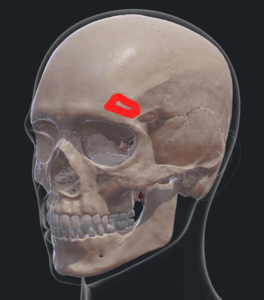

Εξαιρετικά χρήσιμο είναι το ενδοσκόπιο σε όγκους ή εξεργασίες του πρόσθιου κρανιακού βόθρου. Ακόμα και σήμερα οι περισσότεροι νευροχειρουργοί διενεργούν μεγάλες δερματικές τομές και κρανιοτομίες στην μετωπιαία χώρα, οι οποίες μπορούν όμως να αντικατασταθούν από προσπελάσεις κλειδαρότρυπας με τη χρήση του ενδοσκοπίου. Ουσιαστικά ο όγκος που φαίνεται στην εικόνα 7 μπορεί να αφαιρεθεί μέσα από μία μικρή υπερόφρυα προσπέλαση αντί για την κλασσική πτεριονική. Το αποτέλεσμα της εξαίρεσης είναι εξαιρετικό αφού στην περίπτωση του ενδοσκοπίου έχουμε άριστη απεικόνιση του όγκου (βίντεο 1). Η τομή γίνεται στο φρύδι χωρίς αυτό να χρειασθεί να ξυρισθεί, μετεγχειρητικά δε φαίνεται κάποια τομή.